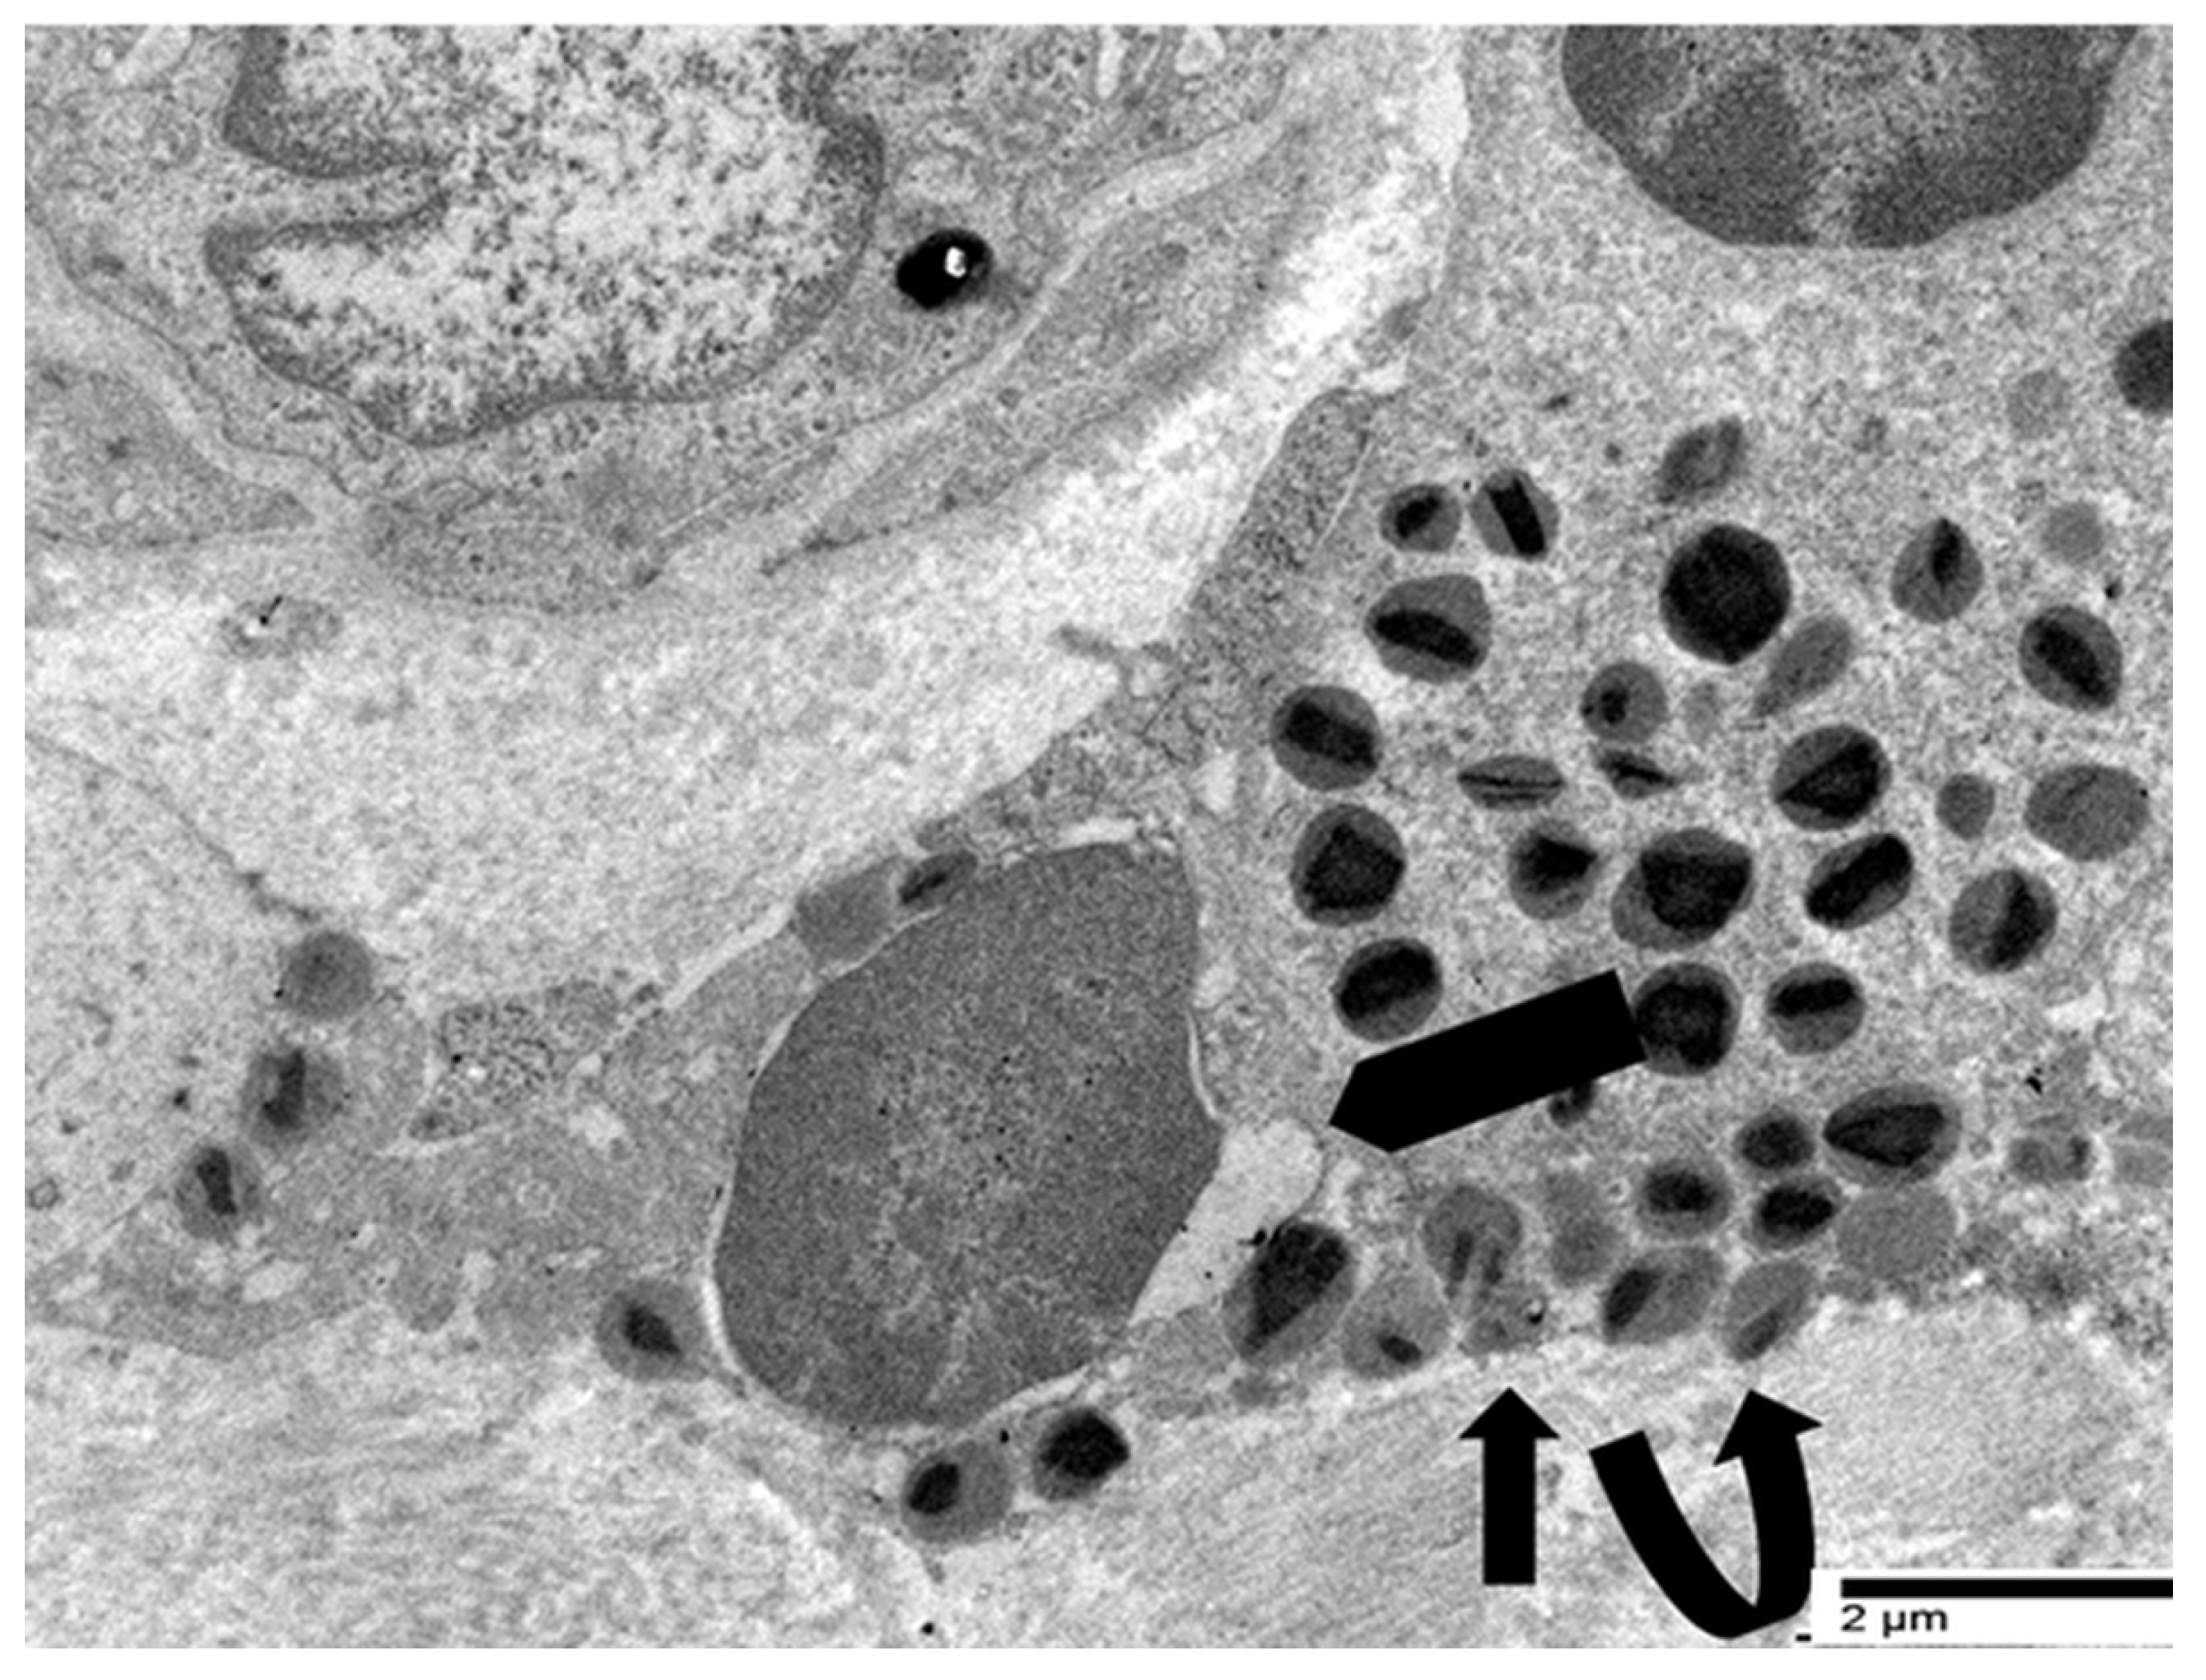

4.3. Our Ultrastructural Observations of Eosinophil ETosis in Gastric Carcinoma

5.2. Ultrastructural Evidence of Eosinophil-Mediated Tumor Cell Injury in Gastric Carcinomas

- Neves, V.H.; Palazzi, C.; Bonjour, K.; Ueki, S.; Weller, P.F.; Melo, R.C.N. In Vivo ETosis of Human Eosinophils: The Ultrastructural Signature Captured by TEM in Eosinophilic Diseases. Front. Immunol. 2022, 13, 938691. [Google Scholar] [CrossRef]

- Caruso, R.; Caruso, V.; Rigoli, L. Ultrastructural evidence of eosinophil clustering and ETosis in association with damage to single tumour cells in a case of poorly cohesive NOS gastric carcinoma. Eur. J. Case Rep. Intern. Med. 2023, 10, 004016. [Google Scholar] [CrossRef]

- Caruso, R.; Caruso, V.; Rigoli, L. Eosinophil cytolysis with or without ETosis in four cases of human gastric cancer: A comparative ultrastructural study. Explor. Target. Antitumor Ther. 2025, 6, 1002309. [Google Scholar] [CrossRef]